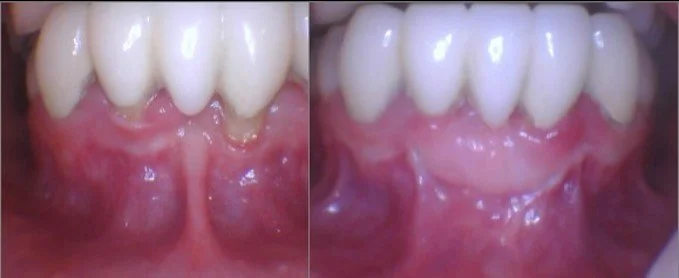

Before

After